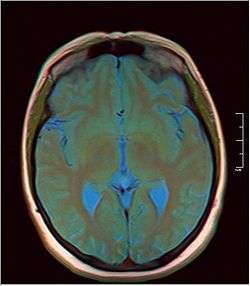

Pineal gland cyst

A pineal gland cyst is a usually benign (non-malignant) cyst in the pineal gland, a small endocrine gland in the brain. Historically, these fluid-filled bodies appeared on 1-4% of magnetic resonance imaging (MRI) brain scans, but were more frequent at death, seen in 21-41% of autopsies.[1] A 2007 study by Pua et al. found a frequency of 23% in brain scans (with a mean diameter of 4.3 mm).[1]

It was once believed that smaller cysts (less than 5.0 mm) were usually asymptomatic, but for larger cysts (greater than 5.0 mm), symptoms could include headache, unexpected seizures, visual disturbances, memory loss, cognitive decline, muscle fasciculations, nausea, weakness, fatigue, light sensitivity, tinnitus, circadian rhythm dysfunction, or hydrocephalus if the cyst impinged on the superior colliculi or caused obstruction of the cerebral aqueduct. Newer research shows that the size of the cyst does not necessarily correlate to the presence of symptoms. In some cases, it will need to be removed before life-threatening situations occur.